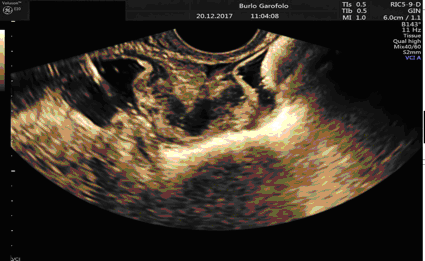

Fig.n.1 Immagine di nodulo vescicale endometriosico in ecografia 3D

L'aggiunta della tecnologia tridimensionale (3D) è relativamente nuova ed alcuni studi hanno dimostrato che questo approccio potrebbe garantire prestazioni migliori rispetto alle immagini bidimensionali classiche, con il vantaggio inoltre di esplorare ed elaborare le immagini non in presenza della paziente, consentendo a più lettori di studiare i dati ecografici. Un ulteriore step aggiuntivo è rappresentato dall’ecografia modificata”. Si effettua a discrezione dell’ecografista per migliorare la definizione diagnostica su indicazione delle localizzazioni di patologia: esame ecografico guidato dal dolore; esame ecografico eseguito con rettosonografia o con la sonovaginografia e l’ecografia tridimensionale. L’ecografia modificata ha dimostrato una migliore definizione diagnostica rispetto alla metodica tradizionale nonostante la scarsità degli studi precluda una valutazione di tipo statistico.

Da un recente consenso internazionale l’ecografia transvaginale emerge come la tecnica di imaging di prima linea grazie alla sua disponibilità e al costo relativamente basso pur presentando solo nelle mani di operatori dedicati un'alta affidabilità diagnostica che tuttavia varia a seconda delle sedi studiate. A differenza di altre tecniche di imaging sfrutta lo studio della dinamicità degli organi che aiuta ad approfondire nello specifico proprio le sedi di maggiore dolorabilità. Tuttavia, soprattutto nello studio dell'endometriosi, la metodica è fortemente operatore-dipendente, la cosiddetta Ecografia Pelvica di II livello.

Un accurato studio delle localizzazioni endometriosiche è di importanza fondamentale per una corretta pianificazione terapeutica che sia medica e/o chirurgica al fine di evitare la progressione di malattia che in stadi avanzati può danneggiare in maniera irreversibile non solo gli organi dell’apparato riproduttivo femminile ma anche organi limitrofi ad esso (vescica ed ureteri, intestino, strutture muscolari e fasciali).